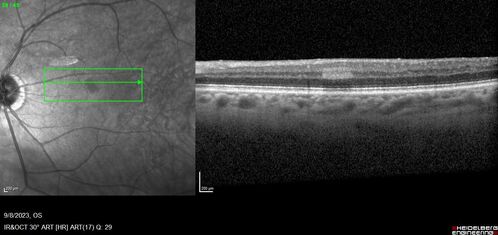

Paracentral acute middle maculopathy - isolated

83 year old man New spot in the vision yesterday left eye.

Medical Hx: Pure Hypercholesterolemia

Systemic Meds: Crestor.

VA OD: Dcc20/20

VA OS: Dcc20/20

IOP: TP: OD:19 OS:10

Isolated PAMM lesion